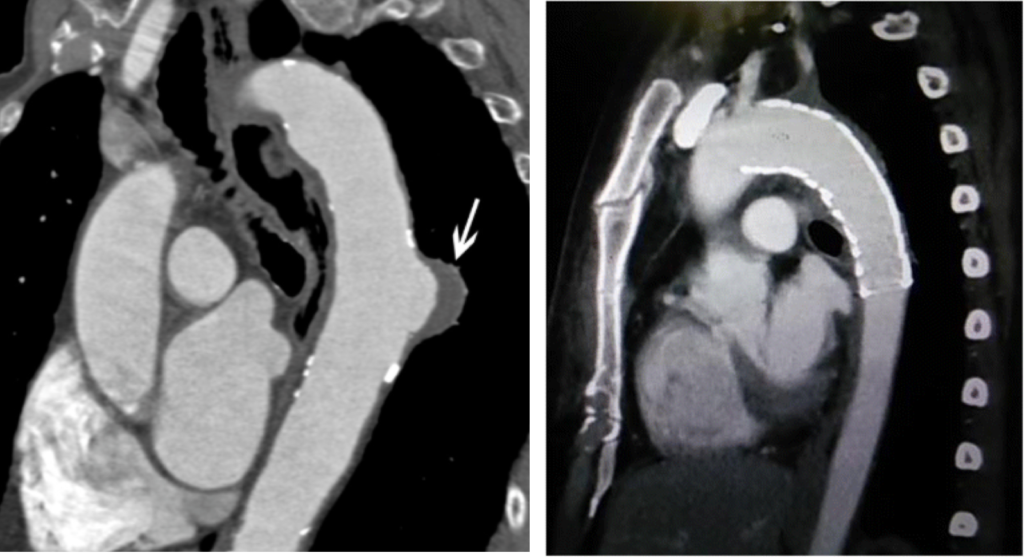

Il existe de nombreuses raisons pouvant expliquer la présence d’un anévrisme au niveau de l’aorte thoracique descendante. La cause principalement retrouvée en est l’athérosclérose. Ces anévrismes sont rarement symptomatiques et le diagnostic est souvent fortuit lors de la réalisation d’un scanner thoracique.

Des contrôles seront systématiques par scanner pour vérifier le bon positionnement avec le temps de la prothèse.